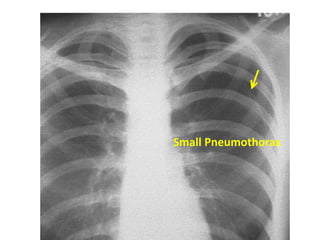

Pneumothorax

Small Pneumothorax